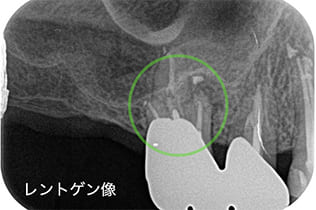

Case04

-

- 原因

- 歯根嚢胞

- 治療内容

- 歯根端切除法

- 治療費用

- ¥110,000

他院で治療した歯が腫れていて、様子を見るように言われたが、なかなか治らない、とのことでご来院された患者さんです。歯根端切除術を行い、腫れもなくなり、経過良好です。

<リスク・副作用>

外科手術のため、術後に出血、痛みや腫れ、違和感を伴います。口腔内の状態によっては適応できないことがあります。歯根端切除で治らなければ抜歯を検討しなくていけない場合もあります。